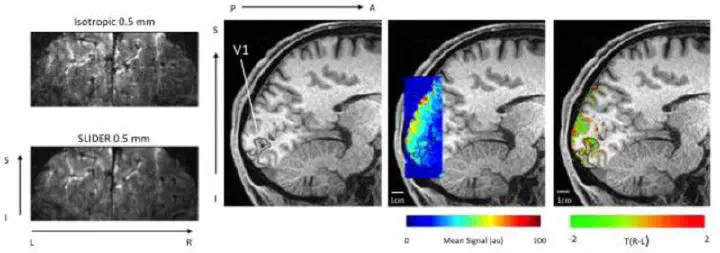

Pushing the limits of ultra-high resolution human brain imaging with SMS-EPI demonstrated for columnar level fMRI